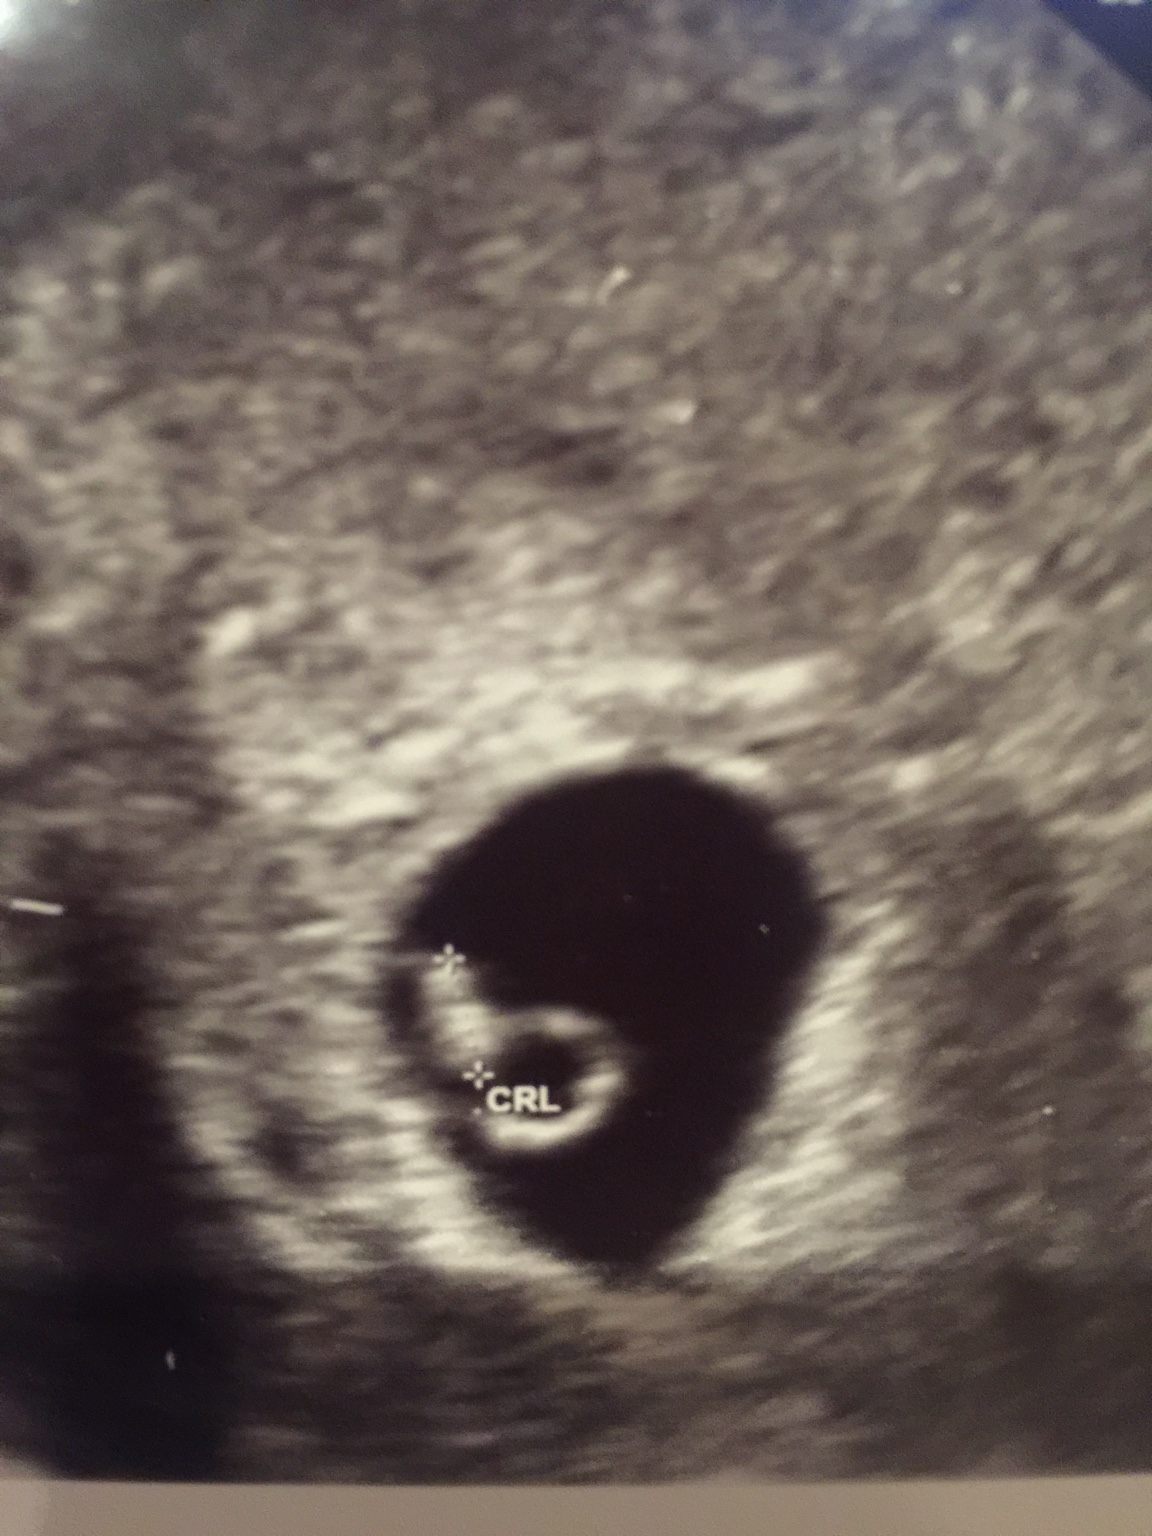

Witam dziewczynki z rana ja już po pierwszej wizycie ciaza potwierdzona całe 0,31 cm szczęścia ale jeszcze tydzień stresów przedemna za tydz idę na kontrole serduszka[emoji173]️ bo zaczęło już bić ale narazie w dolnych granicach mam nadzieje ze się rozkręci

a o to mój kropeczek